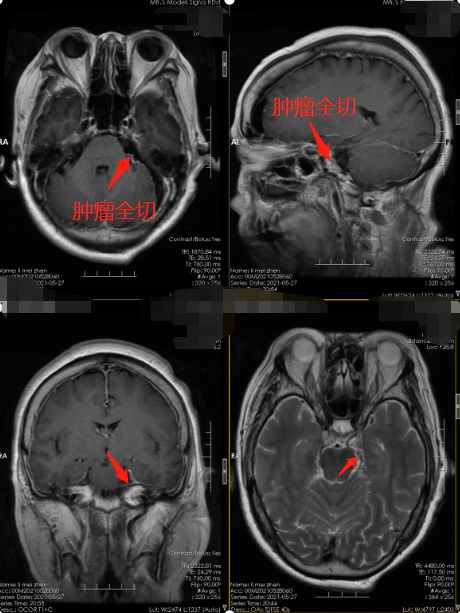

▲术后

入院后完善相关检查,主管医生详细告知病人和家属手术风险,以及确定的手术方式。取得同意后,择期进行了“左侧桥小脑角区占位切除术”,术中全程采用神经电生理监测,术程顺利,术后进监护病房严密监护生命体征。

术后,李阿姨恢复很快,面部麻木感消失,面容两侧对称,还保有靓丽的笑容。